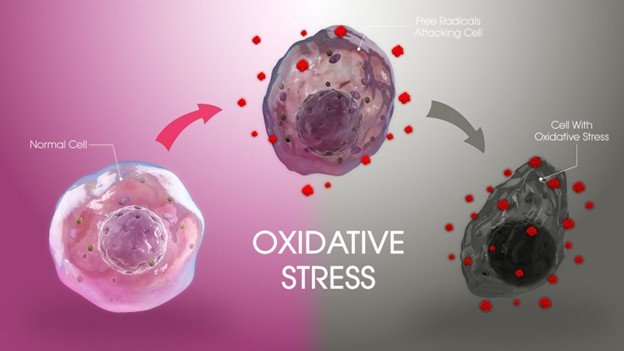

DFUs are open wounds or ulcers that usually develop on the lower part of the foot in diabetic patients. They ocurr due to diabetes complications like peripheral neuropathy (nerve damage), lack of circulation (ischemia), and infection. These ulcers are severe as they raise the susceptibility of infections. It may result in hospitalization, amputation and severe health complication without treatment.

· Poor glycemic control, infection severity, ischemia, and neuropathy aggravate prognosis.